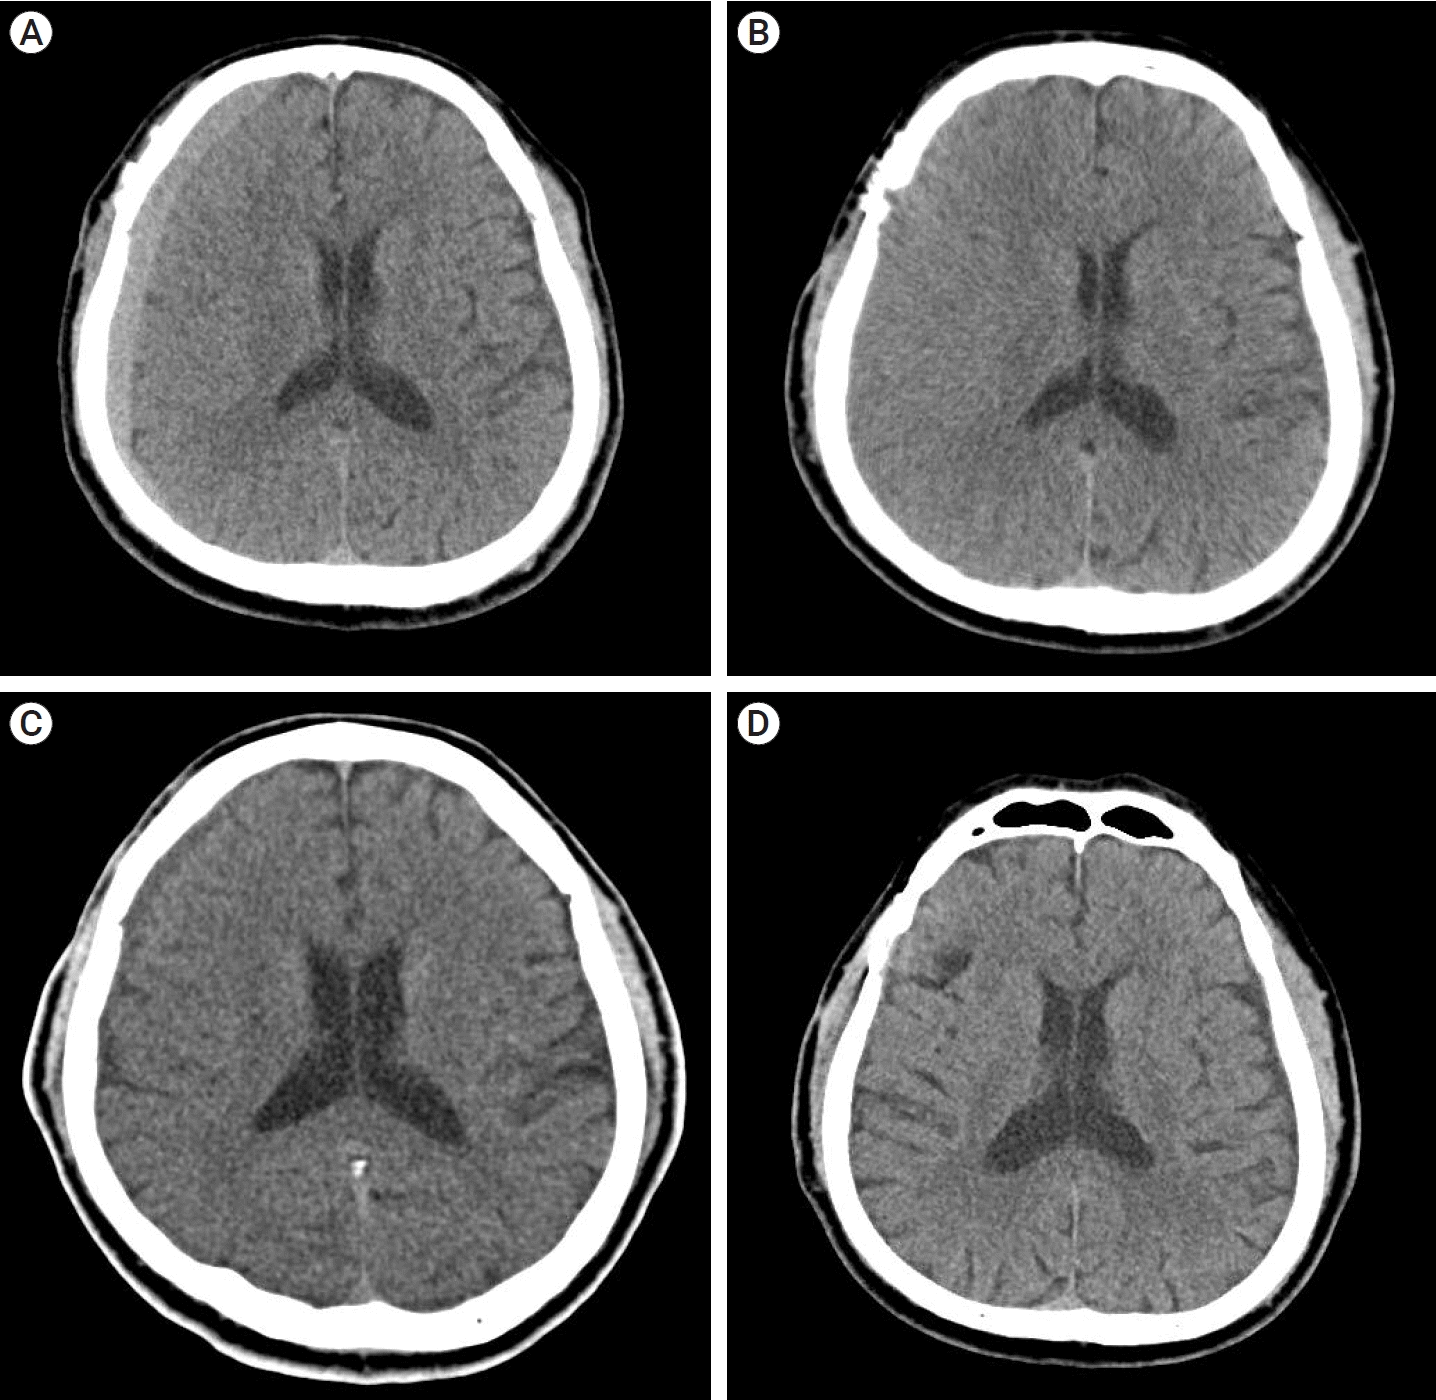

A 57-year-old man underwent surgical clipping for an unruptured right middle cerebral artery (MCA) bifurcation aneurysm. The patient was taking medication for hypertension and pontine infarction. Antiplatelet therapy was stopped for more than 5 days before surgery. The surgery was performed using the ipsilateral pterional approach, and there were no events during the surgery. The patient was discharged without any specific symptoms after surgery. A CT scan taken on the 44th POD showed high-density CSDH in the frontoparietal area (Fig. 3A). The hematoma volume was 78.1 ml, maximum thickness was 17.27 mm, HUs was 58.14, and midline shift was 8.34 mm. The patient was suffering from mild symptoms (MGS=1) and headache symptoms (NRS=2). We recommended that the patient attend an outpatient clinic for 2 weeks and instructed to visit the emergency department whenever neurological symptoms occurred.

CT scans on 58th and 72th POD showed no significant difference except for a slight increase in volume and then decrease again, and there were no neurological symptoms other than mild headache, so we decided to continue outpatient follow-up.

On the 86th day postoperative CT, the hematoma became hypo-dense and significantly decreased in volume, and the symptoms completely resolved (Fig. 3B). The hematoma volume was 32.87 ml, HUs were 3.36, and midline shift was 22.2 mm, CT performed on POD 177 at the outpatient clinic showed complete resolution of the hematoma (Fig. 3C).

Fig. 3.

(A) Axial view of CT scan showing a high-density CSDH in the frontoparietal area (Hematoma volume: 78.1 ml, maximum thickness: 17.27 mm, HUs: 58.14, midline shift: 8.34 mm). (B). CT scan of 4th OPD showing CSDH had changed from high-density to hypo-density (Hematoma volume: 32.87 ml, HUs: 3.36, midline shift: 22.2 mm). (C) CT scan of 5th OPD showing complete resolution of CSDH. CT, computed tomography; CSDH, chronic subdural hematoma; HU, hounsfield units; OPD, outpatient department